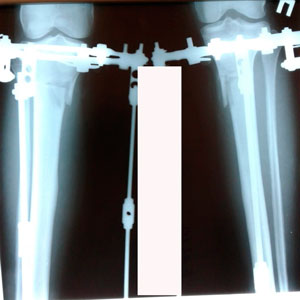

Исходник - 38 лет.

Дата операции - 18.02.2020